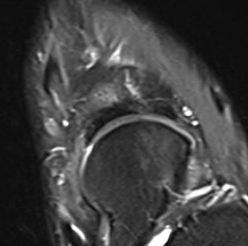

MRI

Minimally displaced navicular stress fracture